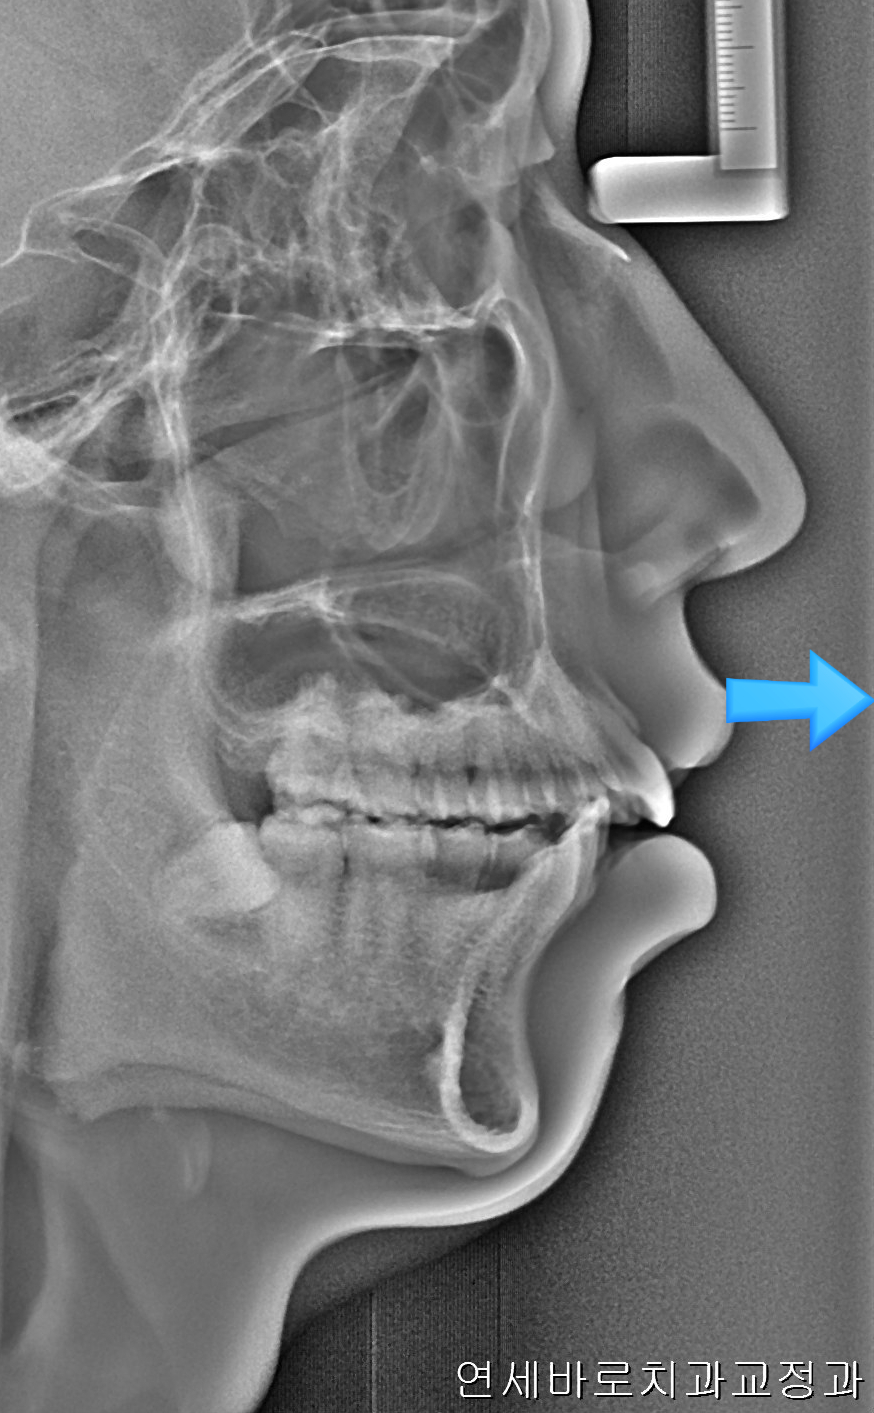

환자분은 심한 무턱과 단안모의 형태를 가진 안모의 소유자였습니다.

이런 분들은 자칫 입이 과하게 들어가면 안모가 많이 안좋아질 수 있죠.

환자분과 상담 후 비발치로 최대한 입을 넣기로 했습니다.

과연 얼마나 들어갔으려나 천천히 보겠습니다.